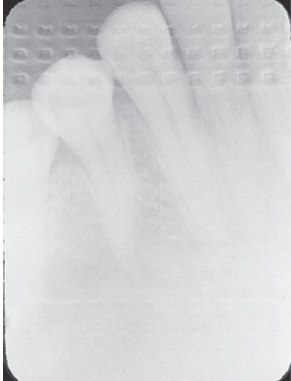

What is the problem with this Phalangioma X-ray?

May occur with digital sensors or film,Patient’s finger was positioned in front of the receptor during finger-holding method

How would you resolve this Phalangioma X-ray?

Never allow the patient to hold a receptor during exposure